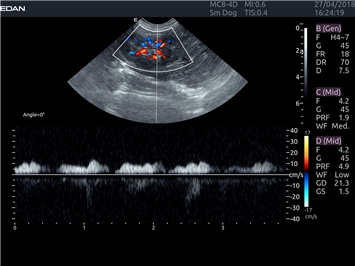

Импульсно-волновой допплер:

Да

Дуплексное сканирование: